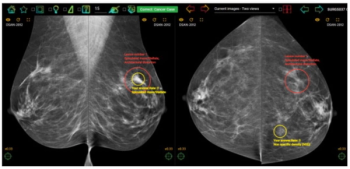

A symptomatic first breast cancer diagnosis, prevailing breast density at a second breast cancer diagnosis and trabecular thickening on surveillance mammography were linked to mammogram-occult ipsilateral breast cancer, according to new research.

In a study looking at the impact of experience and case volume of breast screening radiologists, researchers found that reviewing more than 150 cases per week was necessary to achieve an 80 percent rate of true-positive assessments for malignant calcifications.

While researchers noted no significant impact on sensitivity rates, they found that access to a patient’s prior mammograms resulted in a nearly 15 percent increase in sensitivity for current mammography interpretation.

In a study involving over 272,000 breast cancer screening exams, digital breast tomosynthesis (DBT) had a higher breast cancer detection rate and a lower rate of advanced cancer presentation at the time of diagnosis in comparison to digital mammography.